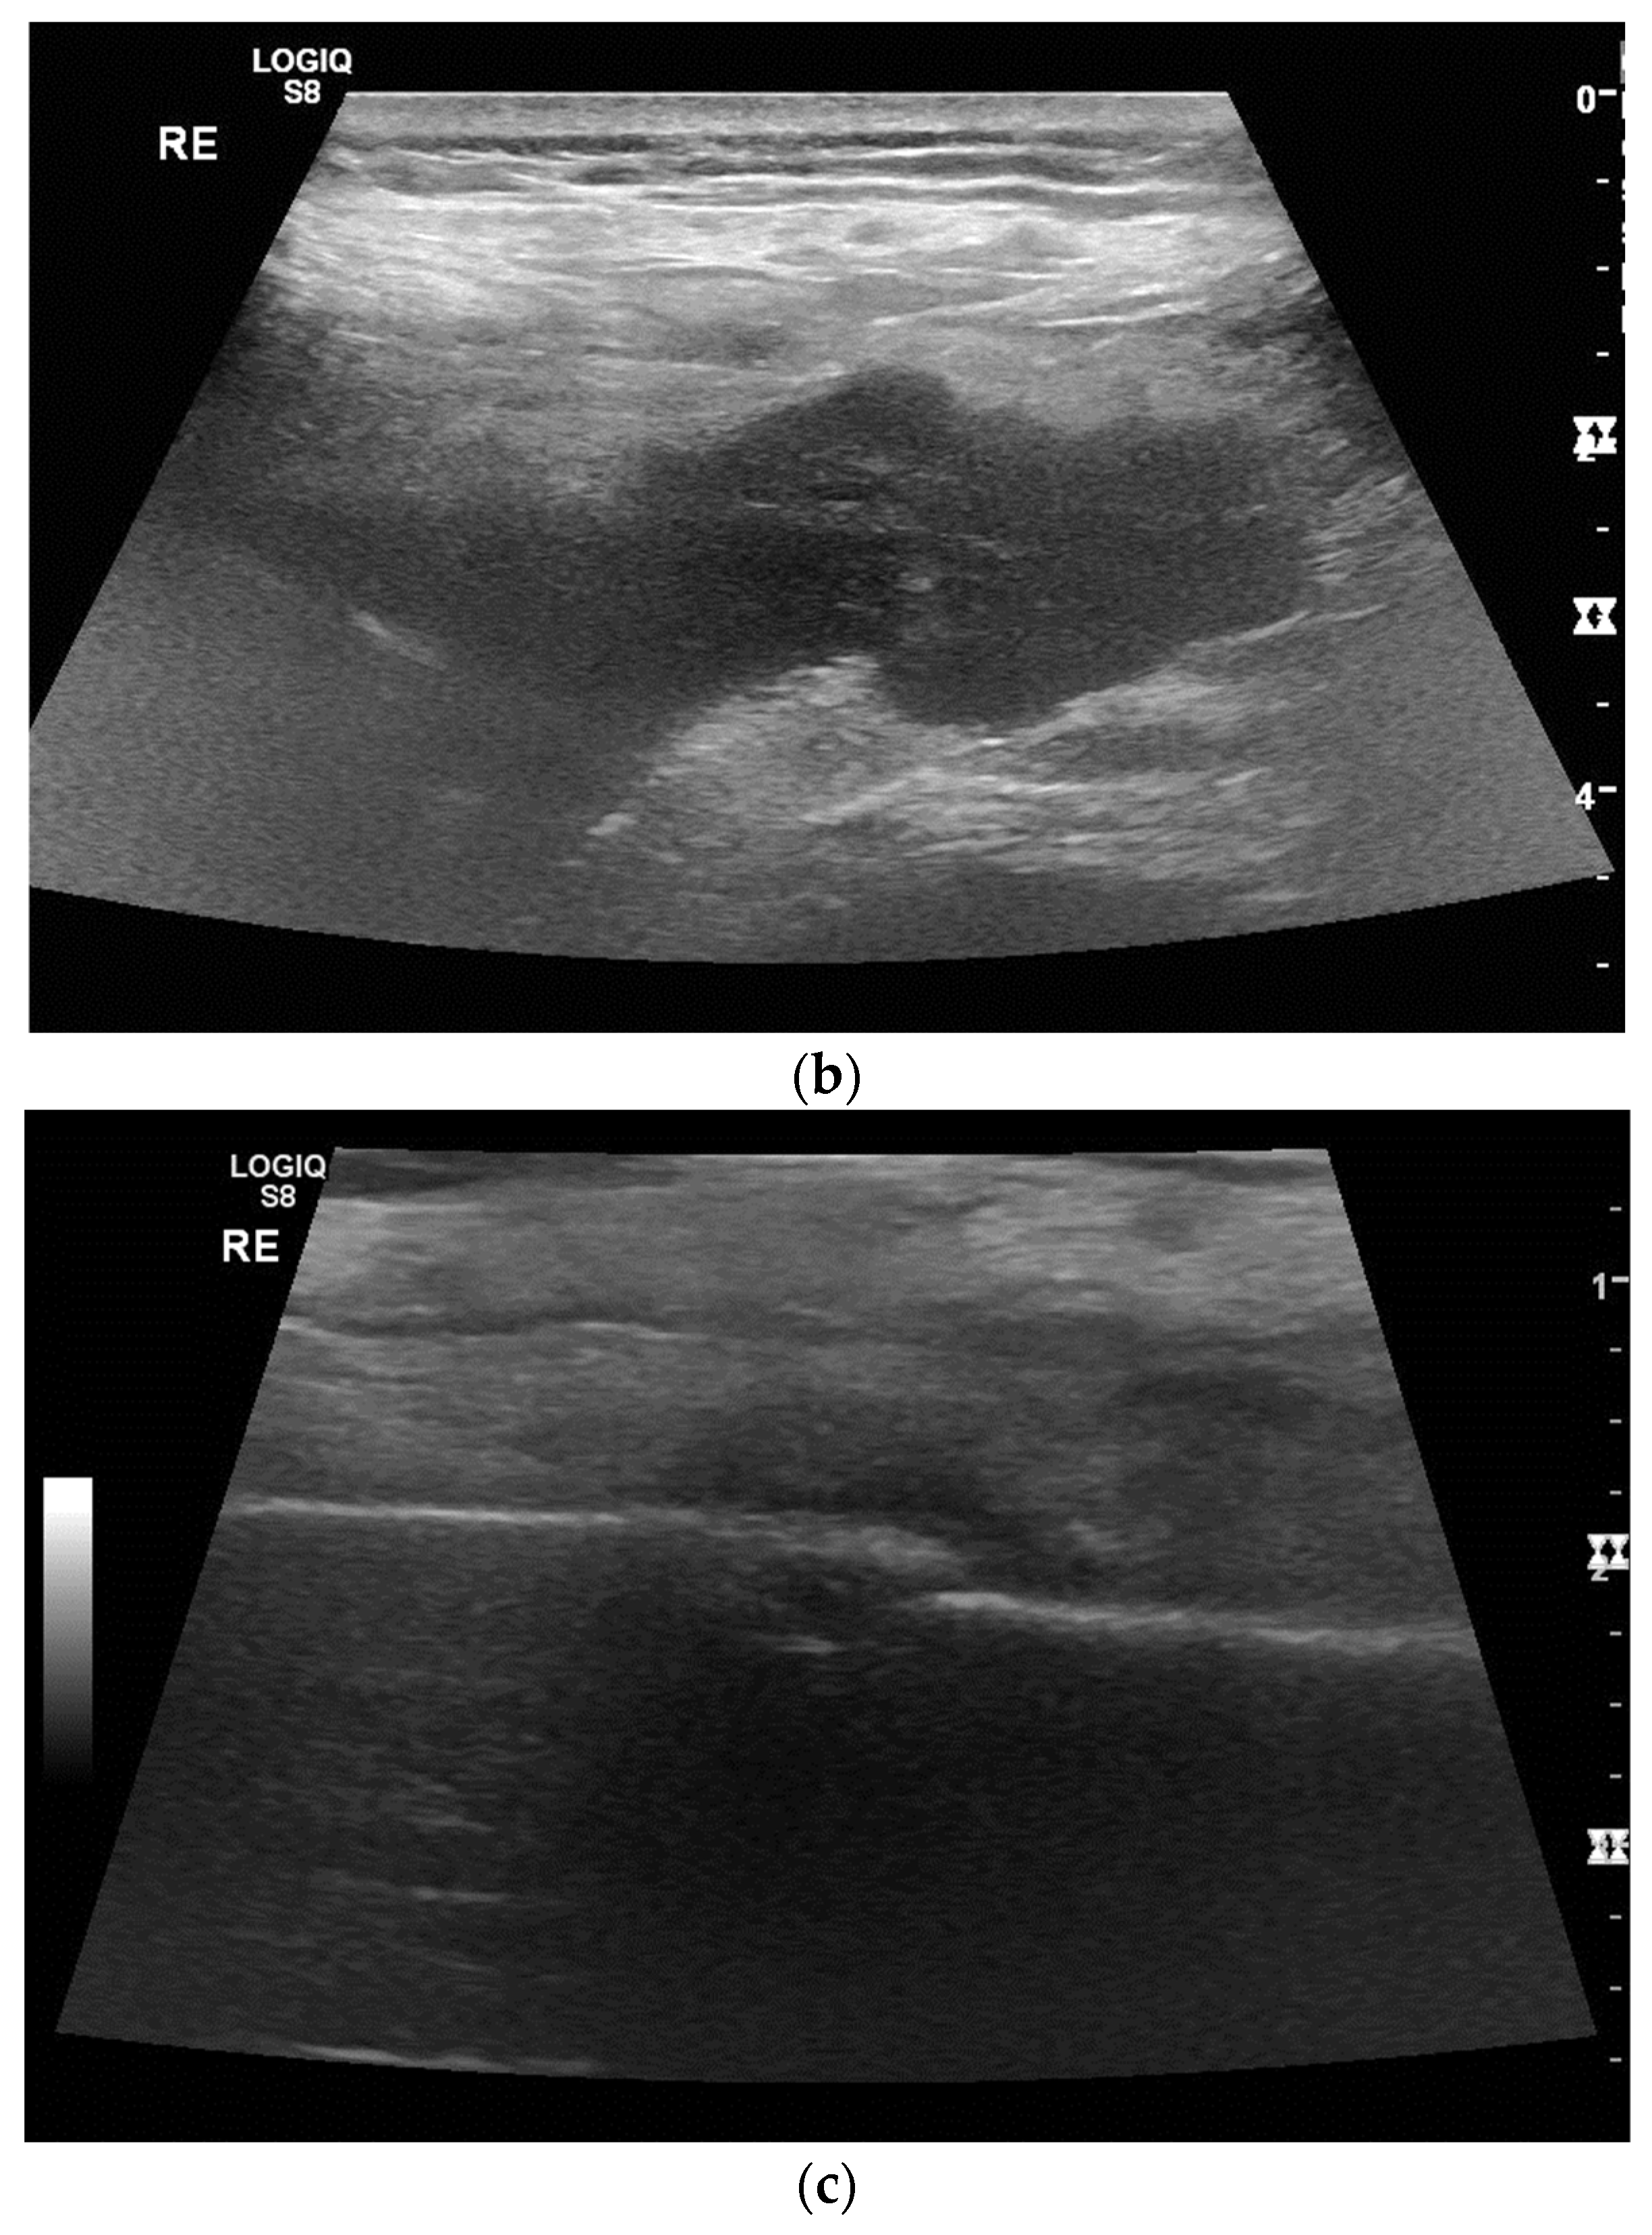

3. Pleural Mesothelioma